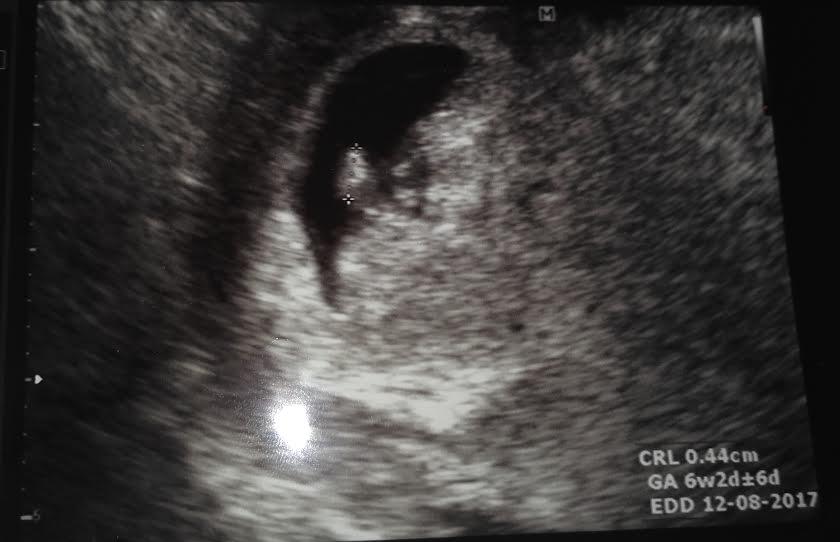

Jinak já jsem po 1. IVF, už 7. den od ET jsem měla //, minulý týden na UTZ potvrzeny dvě bublinky, dneska jsem 5tt+4 a už se do ničeho nevejdu - mám dojem, že s dvojčátkama bude všechno mnohem intenzivnější a rychlejší 😀

Pustila ulz a 2 kuličky

Z toho 1 je plná odpovídá na den 6+2 má srdíčko a další dutinka je menší a plod je málo patrný bez sdicka

Napsala mi syndrom mizijiciho dvojčete

Já mám 1 dutinku s 6+2 a druhá odpovídá mín a plod nebyl patrný, ale je prý dobře, že mám každý váček zvlášt. Že by neměl ohrozit toho zdatného jsou pdo sebou, nemám to na fotce, asi mně nechtěla lákat, myslí si fakt že zanikne.